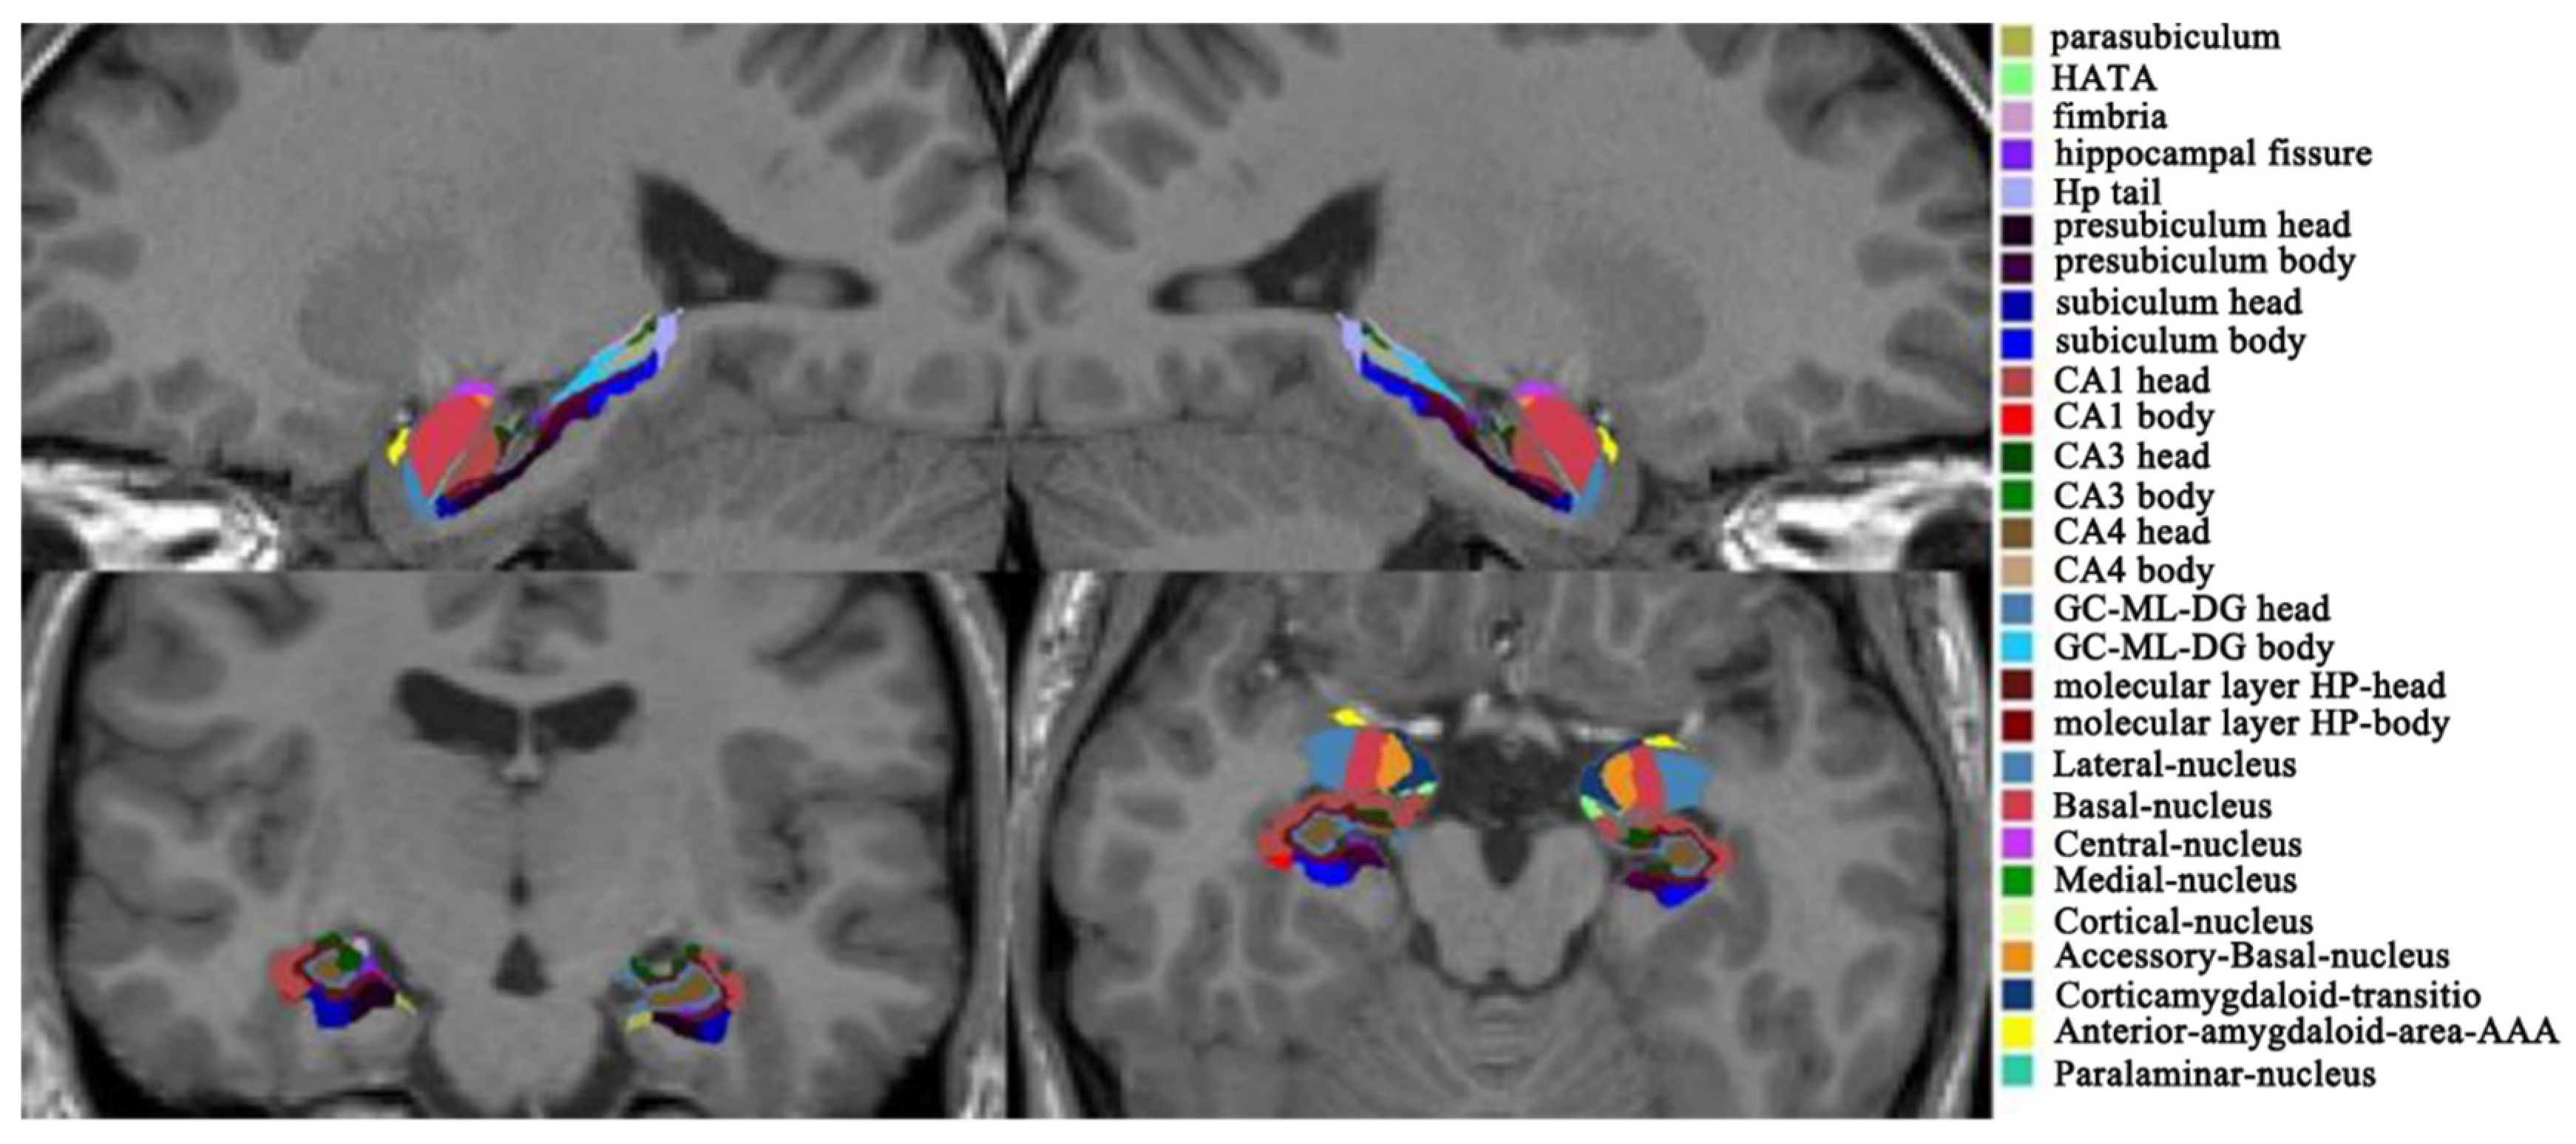

3.1. Hippocampal and Amygdala Subfields

- Iglesias, J.E.; Augustinack, J.C.; Nguyen, K.; Player, C.M.; Player, A.; Wright, M.; Roy, N.; Frosch, M.P.; McKee, A.C.; Wald, L.; et al. A computational atlas of the hippocampal formation using ex vivo, ultra-high resolution MRI: Application to adaptive segmentation of in vivo MRI. NeuroImage 2015, 115, 117–137. [Google Scholar] [CrossRef] [PubMed]

- Saygin, Z.; Kliemann, D.; Iglesias, J.E.; van der Kouwe, A.; Boyd, E.; Reuter, M.; Stevens, A.; Van Leemput, K.; McKee, A.; Frosch, M.; et al. High-resolution magnetic resonance imaging reveals nuclei of the human amygdala: Manual segmentation to automatic atlas. NeuroImage 2017, 155, 370–382. [Google Scholar] [CrossRef]